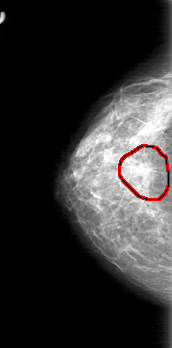

D_4030_1.RIGHT_MLO

RIGHT_MLO LINES 5281 PIXELS_PER_LINE 2476 BITS_PER_PIXEL 12 RESOLUTION 43.5 OVERLAY

FILE: D_4030_1.RIGHT_MLO.OVERLAY

TOTAL_ABNORMALITIES 1

ABNORMALITY 1

LESION_TYPE MASS SHAPE IRREGULAR MARGINS SPICULATED

ASSESSMENT 5

SUBTLETY 5

PATHOLOGY BENIGN

TOTAL_OUTLINES 1

BOUNDARY